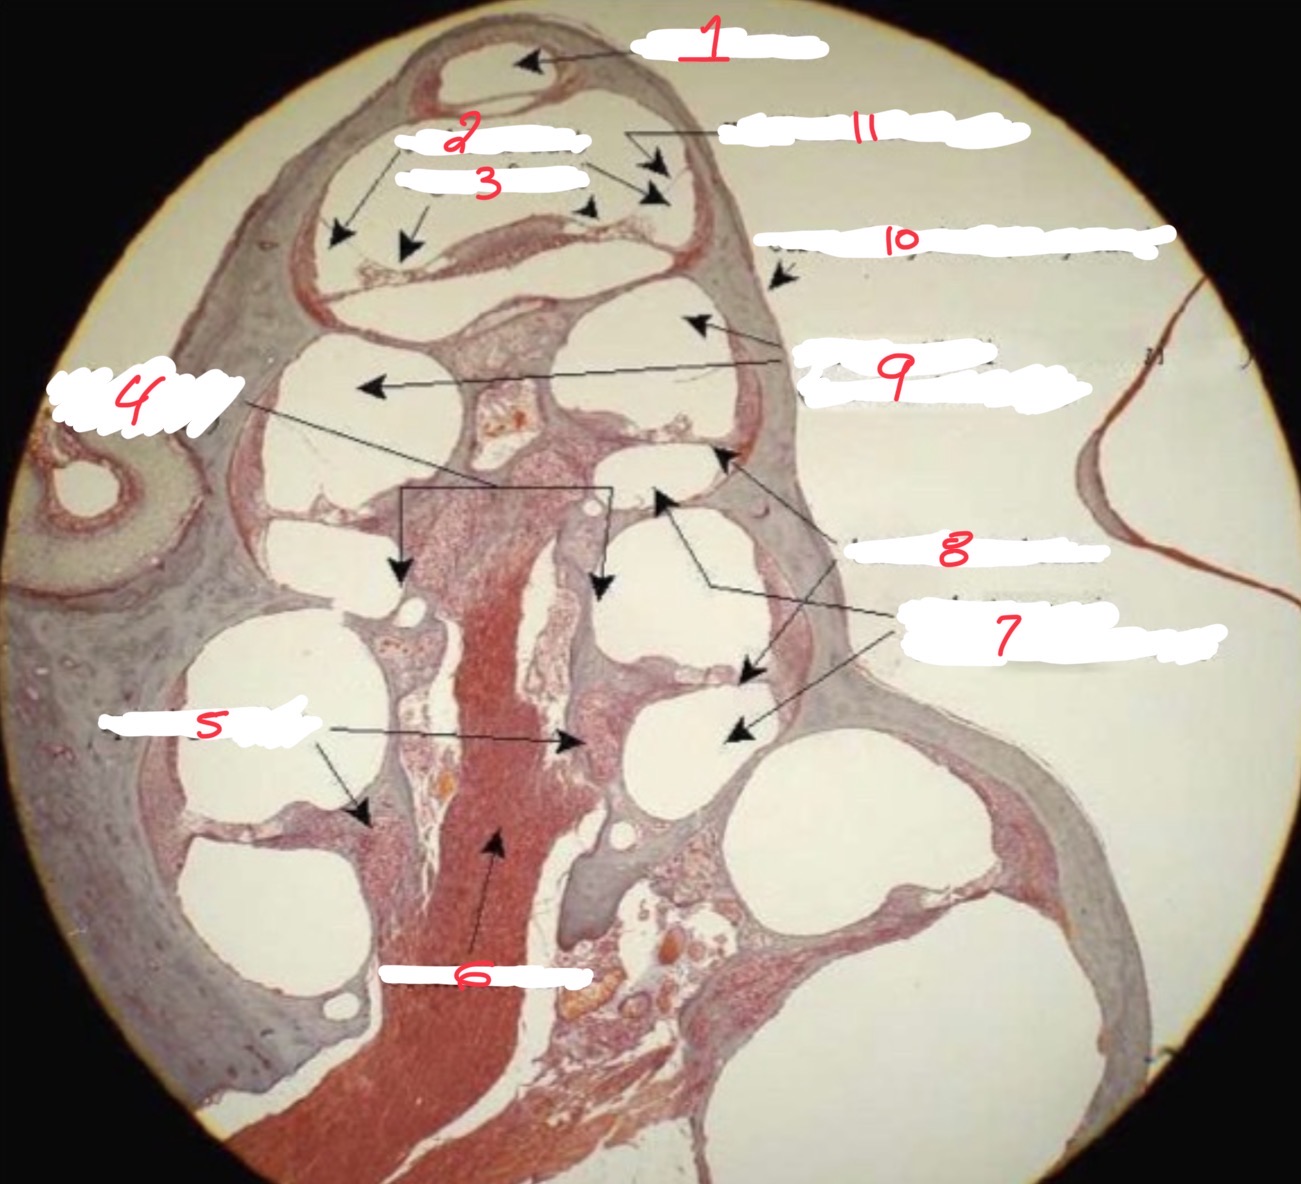

1

Helicotrema

2

Cochlear duct

3

Organ of corti

4

spiral lamina

5

Spiral ganglion

6

Cochlear nerve

7

Scala tympani

8

Basilar membrane

9

Scala vestibuli

10

Osseus labyrinth

11

Vestibular membrane